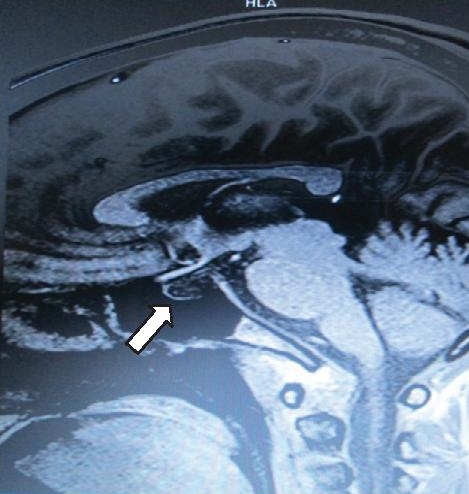

On physical examination, the patient appeared chronically ill with depressed sensorium (Glasgow coma scale E3V3M5). She was afebrile, with stable vital signs (pulse rate 72 beats/min, regular; blood pressure 100/70; respiratory rate 20 cycles/min). She had dry, rough and cold skin, with good turgor. She had pale palpebral conjunctivae and absent axillary and pubic hairs. Laboratory tests revealed normocytic, normochromic anemia with low hemoglobin concentration (7.8 g/dL). She had hyponatremia (109 mmol/L) and hypoglycemia (40 mg/dL), normal potassium (3.9 mEq/L) and creatinine (0.6 mg/dL), top normal urea (20 mg/dL) and low serum osmolality (233 mOsm/kg). Arterial blood gas analysis revealed pH 7.424, PO2 146.9 mmHg and PCO2 24.9 mmHg. Urine electrolytes showed natriuresis (urinary sodium 273 mmol/24 hours, normal value 40-220 mmol/24 hours) and normal potassium excretion (urinary potassium 20.3 mmol/24 hours, normal value 15-125 mmol/24 hours). Basal hormonal workup showed low levels of growth hormone (GH), prolactin (PRL), luteinizing hormone (LH) and follicle stimulating hormone (FSH); and normal cortisol. She also had low free triiodothyronine (FT3) and normal thyroid stimulating hormone (TSH) (Table 1). Magnetic resonance imaging (MRI) of the brain showed an empty sella appearance, with the small-volume pituitary gland flattened against the sellar floor (Figure 2). These findings confirmed the diagnosis of Sheehan's syndrome.

Figure 2. Sagittal enhanced T1-weighted magnetic resonance image showing empty sella appearance, with the pituitary gland flattened against the sellar floor.

The main radiologic finding of SS is the image of an empty sella (seen in 70% of patients) or partially empty sella (30%). The time-dependent evolution of the findings on MRI in SS has been observed to begin acutely with non-hemorrhagic changes in signal intensity consistent with central infarction, along with peripheral and heterogeneous central enhancement in an enlarged pituitary gland. The findings are consistent with patchy central ischemic necrosis in an enlarged gland and are followed by pituitary gland atrophy and an empty sella. These findings on MRI characterize SS and provide early confirmation of the clinical diagnosis.[26]-[28] In our patient, we found a widened sella turcica with a flattened pituitary gland consistent with an empty sella.